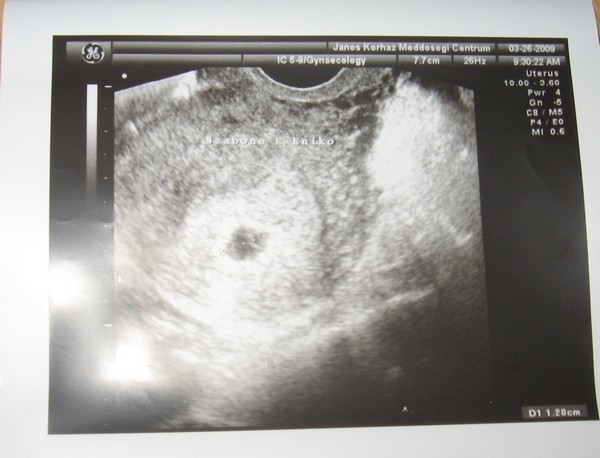

Meg volt az uh. 12mm-es petezsákunk van :lol: De van mellette v.mi alvadt vér.... :?: azt mondta Tanár úr lehet a beágyazódástól, Vagy ezt csak én agyaltam :oops: esetleg a másik embrió akart ott v.mit.....???

És a kistesó első sztárfotója

Áfonyácska: Gratulálok, szép nagy petezsák!!!! A lényeg, hogy ott van a Babóca! Első sztárfotó a KISTESÓRÓL!!! Remélem a véralvadék gyorsan felszívódik majd!!!! Pihenj sokat és vigyázz magatokra! :) :)

Nagyon édi a kistesó! 1,20 ? Olyan érdekes hogy ilyen kis pici sejtből milyen nagy lovak leszünk! :lol: :lol: :lol:

Nem hematómát mondott? Sztem a másik baba is elindulhatott és még nem szívódott fel teljesen. Nem lesz belőle baj, ne izgulj.